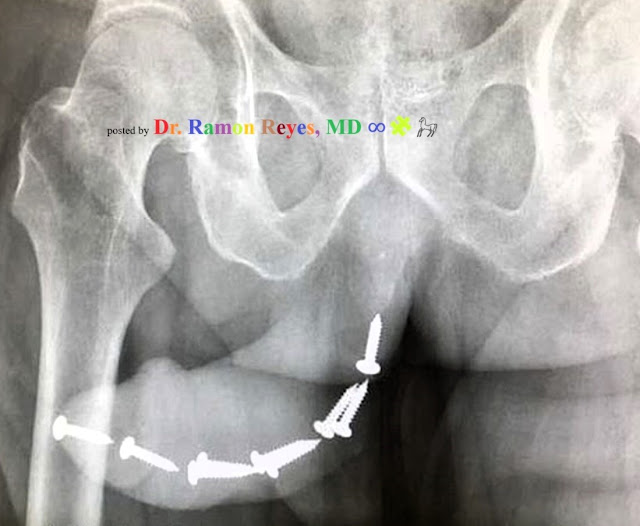

Diagnostico e historia en el enlace

posted by Dr. Ramon Reyes, MD ∞🧩https://www.facebook.com/photo/?fbid=896547718507980&set=a.540372527458836